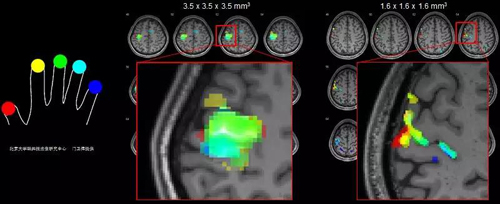

1、亚毫米高清脑成像

Prisma在硬件方面追求极致,是目前唯一一款可同时稳定实现最大梯度场强80和最大梯度切换率200的产品化磁共振,配备了64通道神经功能学专用线圈,使图像的信噪比和分辨率达到3T磁共振的极致,实现了亚毫米高清脑功能成像,精准定位功能区,辅助神经外科设定精细手术方案,同时还可以避免皮层病变的漏诊和误诊,从而精确诊断。

3.jpg